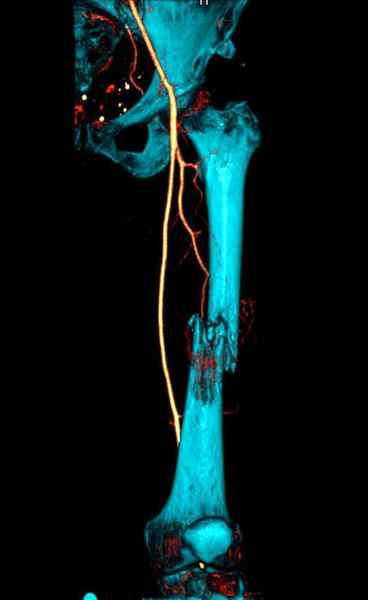

Для предупреждения кровотечения во время рассверливания, за день до операции провели эмболизацию сосудов питающий метастаз. http://radiology.rsnajnls.org/cgi/reprint/150/3/673.pdf (7-11, 12-15-16)

С минимальным рассверливанием и ретроградным методом провели остеосинтез бедра 12 мм гвоздем. (17-20)

Кровопотеря во время операции меньше 100 мл.